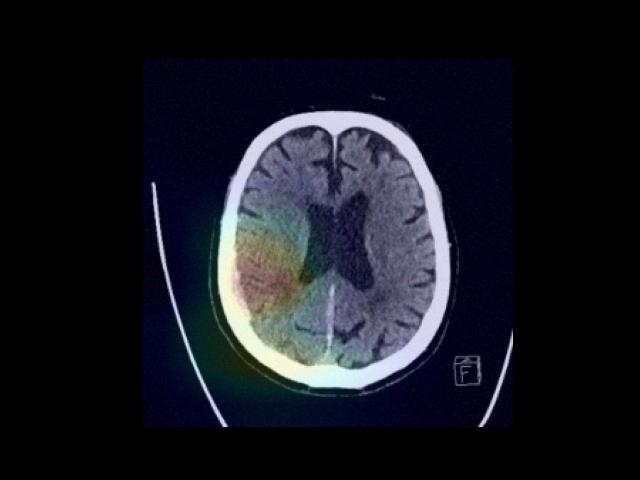

Sample Gallery